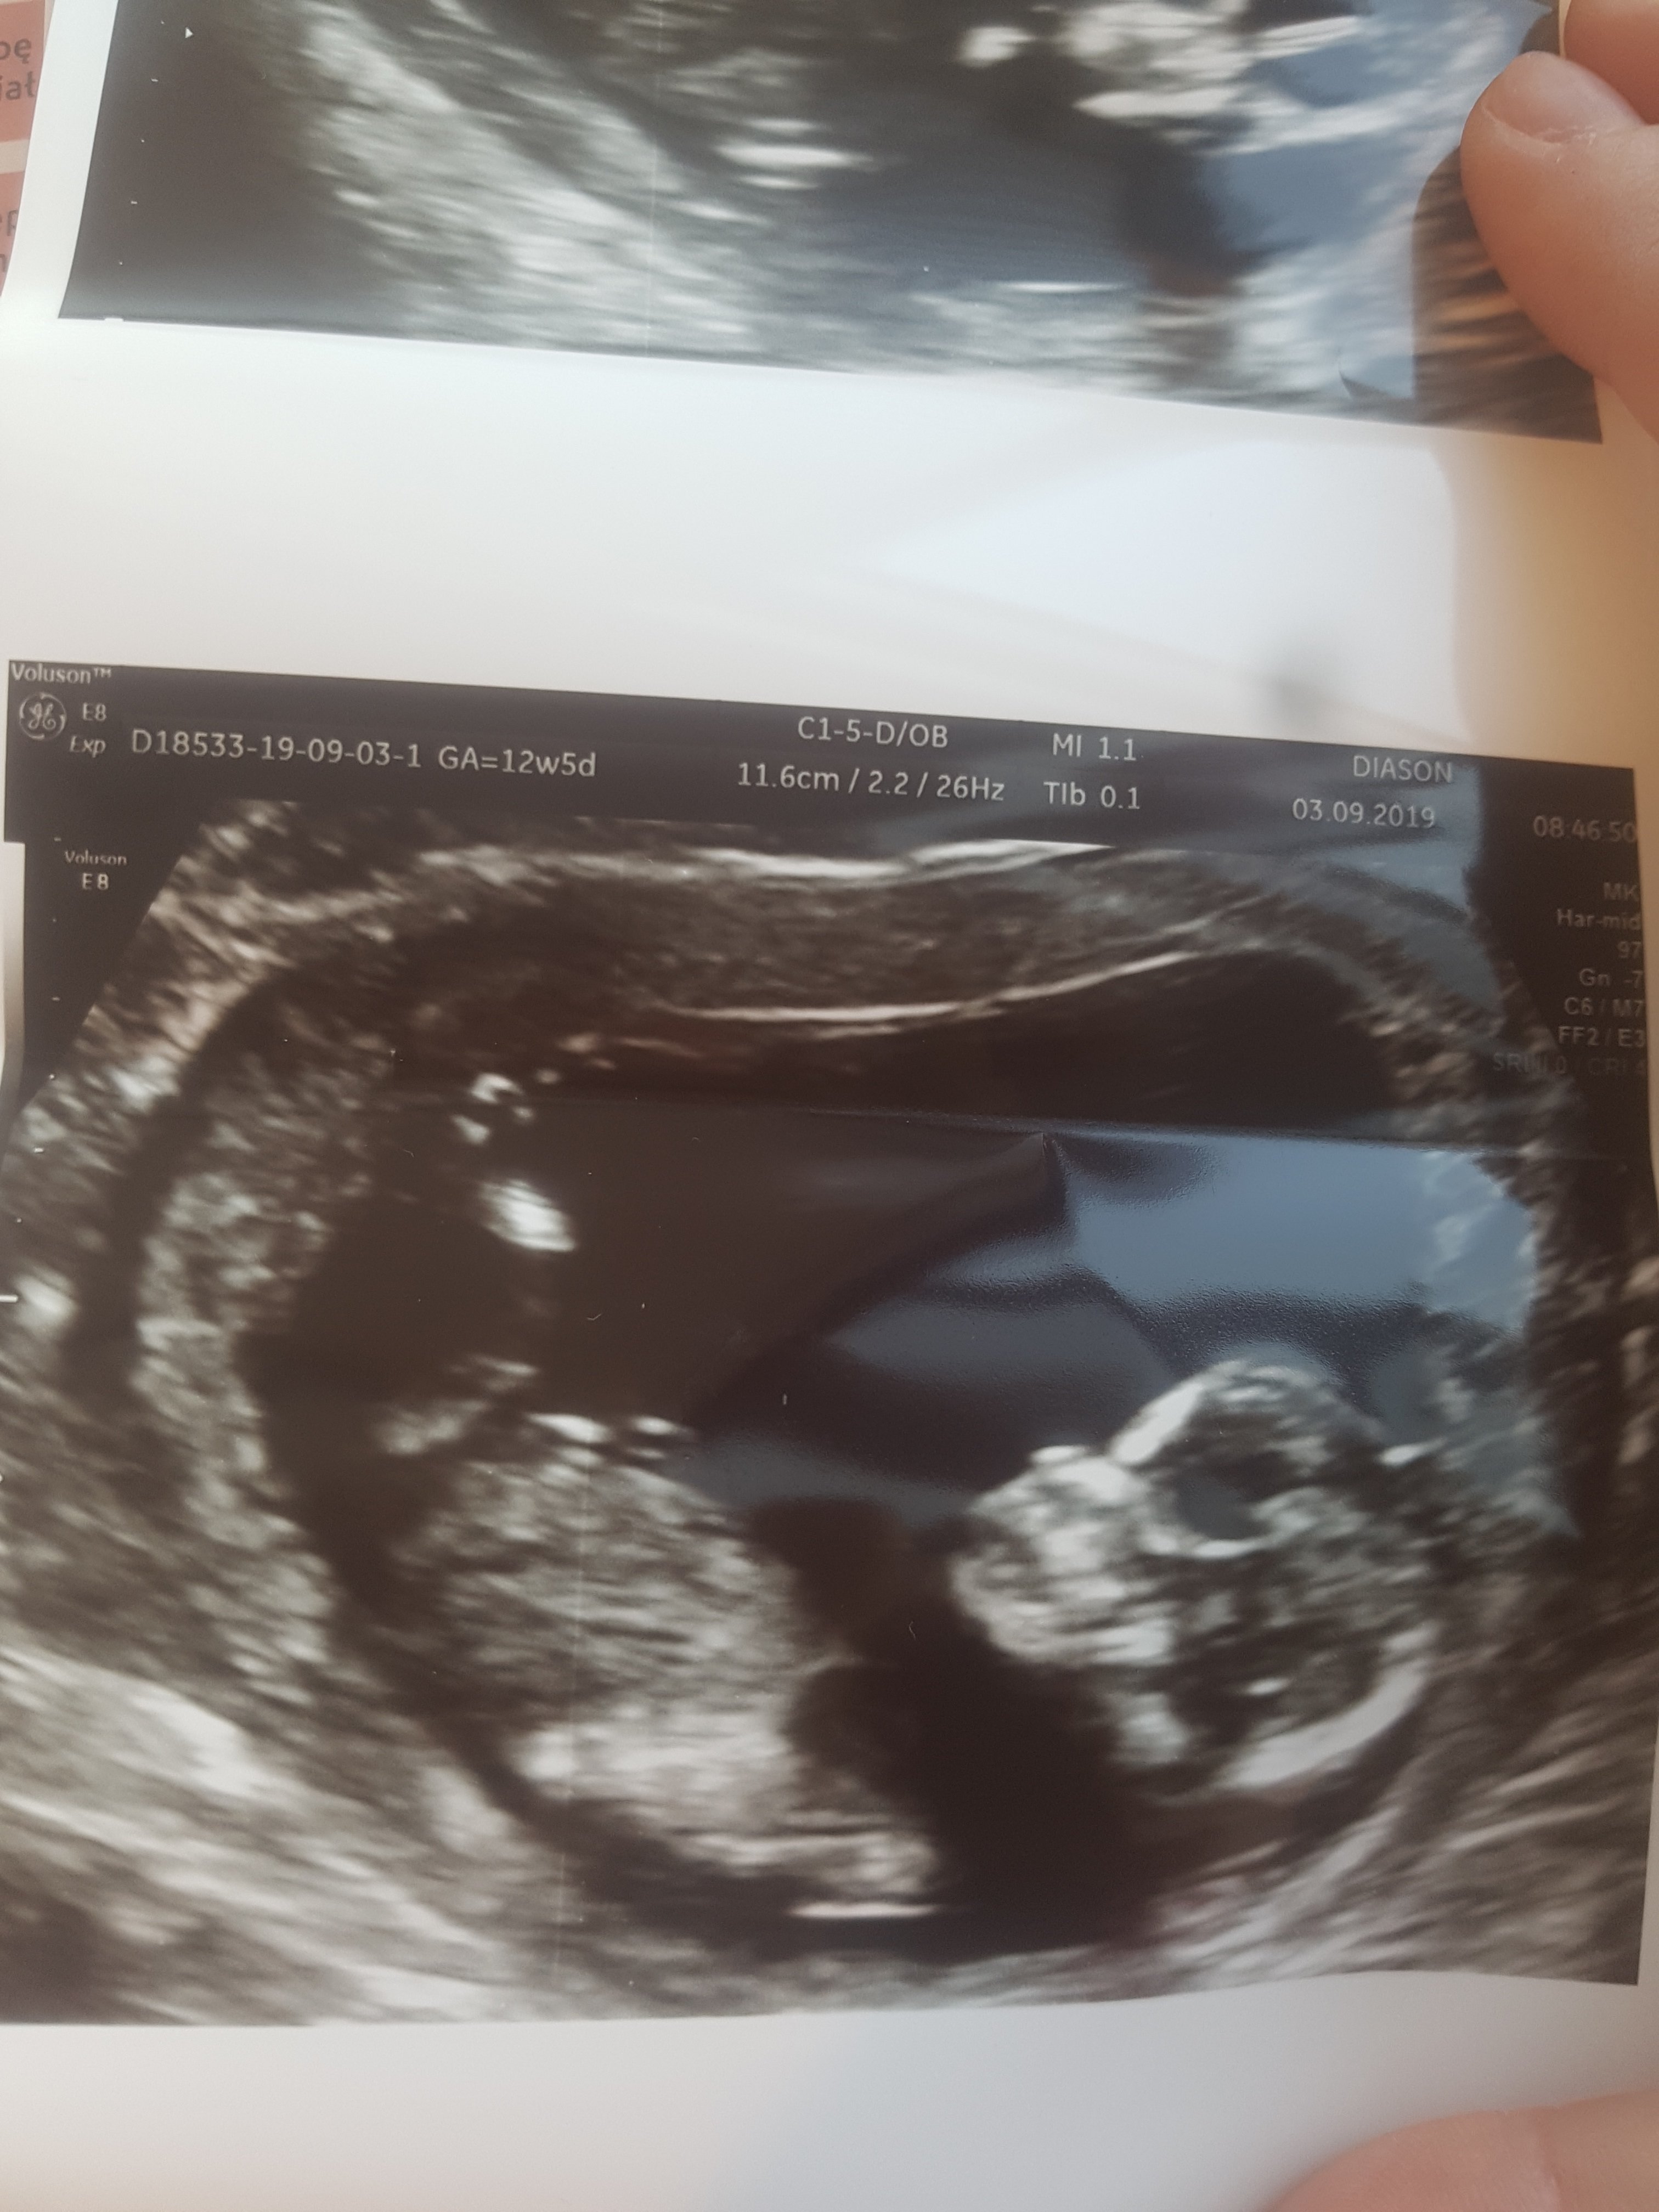

Ja juz po, wszystko super :) :) :)

CRl prawie 7 cm i do tego dlugaśne nogi :D

Wszystkie narządy są prawidlowie, dzidziuś rozwija się książkowo :) wg OM 12+5, z usg 13+1 :) powiedział żeby się nie sugerować za bardzo jego opinią ale wg niego to dziewczynka :)

20190903_100550.jpg

• 20190903_100550.jpg

955,8 KB · Wyświetleń: 80